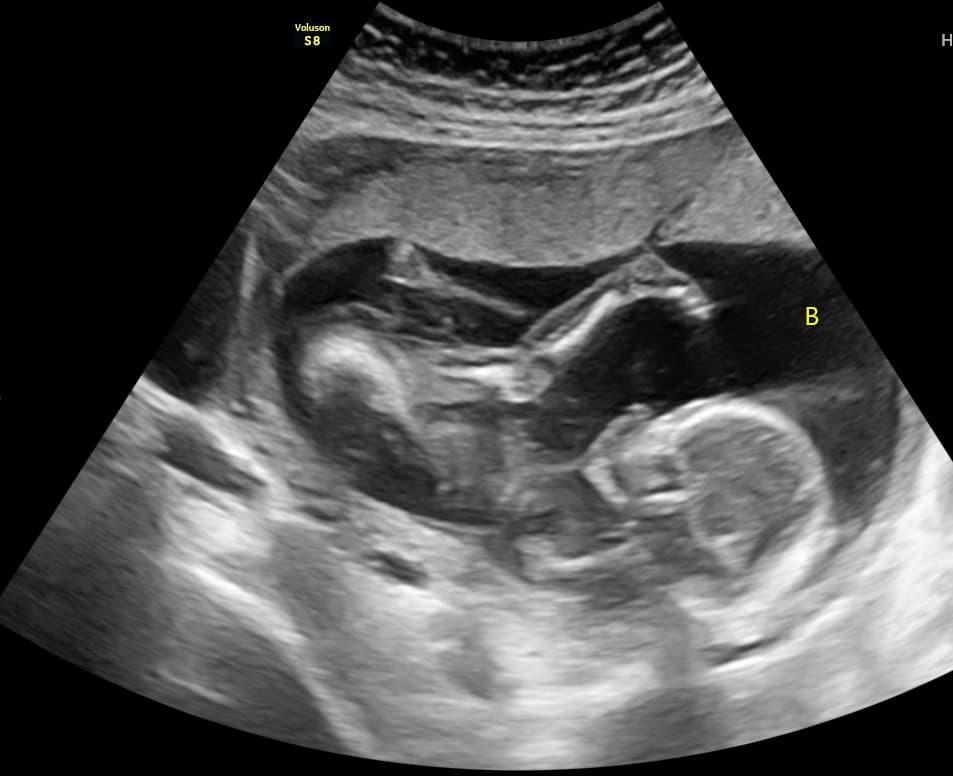

Við bjóðum uppá sónarskoðanir á meðgöngu, snemmsónar, tvívíddar- og þrívíddarsónar og stuttan 15 mínútna sónar.